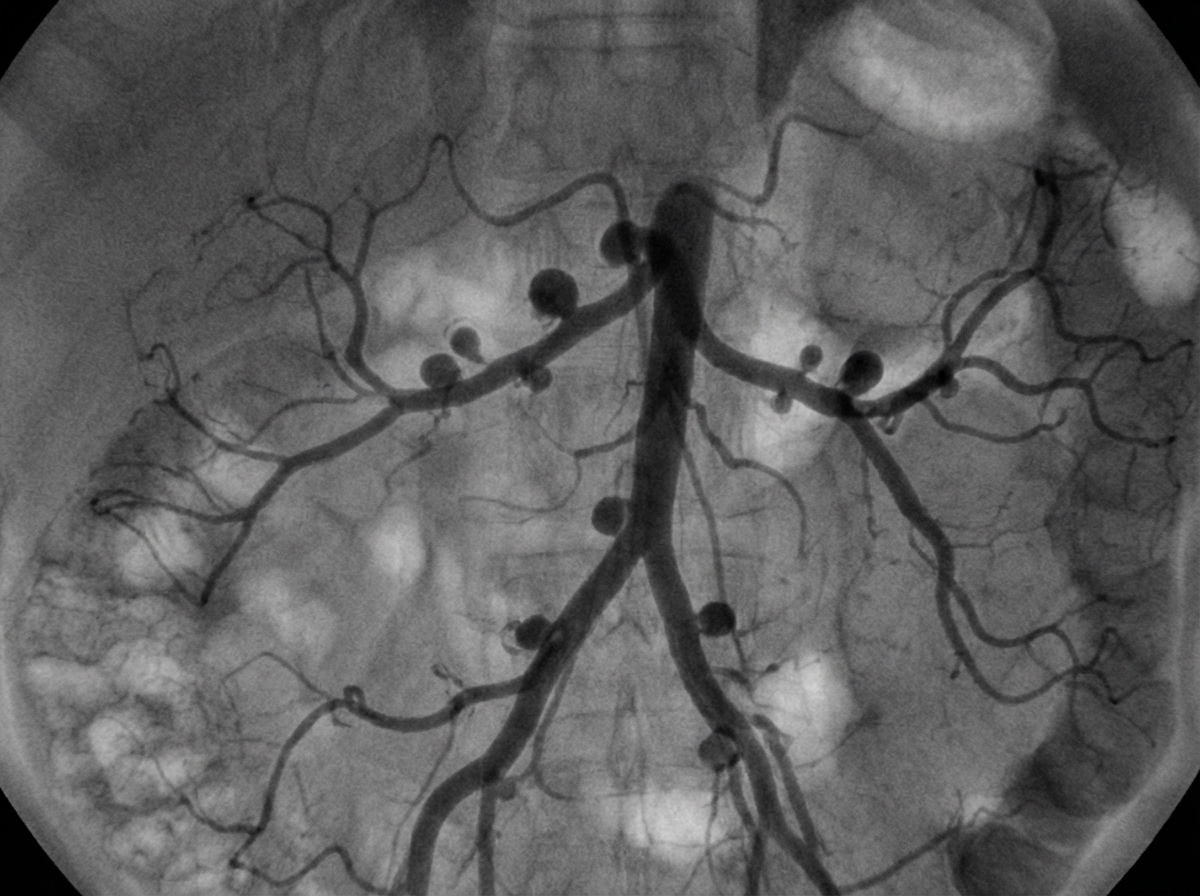

Which condition is most likely associated with the following angiography findings?

Explanation: ***Polyarteritis nodosa*** - Classic angiographic finding shows **multiple microaneurysms** at branch points of medium-sized vessels, particularly in **renal**, **hepatic**, and **mesenteric arteries**. - The **"beading" or "rosary" appearance** on angiography is pathognomonic for PAN, caused by segmental necrotizing inflammation. *Kawasaki disease* - Angiographic findings typically show **coronary artery aneurysms** rather than systemic vessel involvement. - Affects **large coronary arteries** in children, not the medium-sized visceral vessels characteristic of PAN. *Takayasu arteritis* - Angiography reveals **smooth stenosis** and **occlusions** of large vessels like the **aorta** and its major branches. - Shows **long segment narrowing** without the multiple small aneurysms seen in PAN. *Giant cell arteritis* - Primarily affects **large vessels** including the **temporal**, **ophthalmic**, and **vertebral arteries**. - Angiographic findings include **smooth stenosis** and **occlusions**, not the microaneurysmal pattern of PAN.